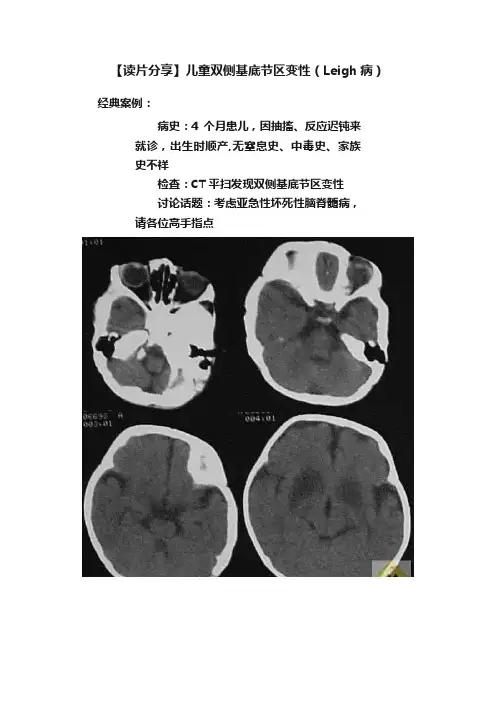

【读片分享】儿童双侧基底节区变性(Leigh病)经典案例:病史:4个月患儿,因抽搐、反应迟钝来就诊,出生时顺产,无窒息史、中毒史、家族史不祥检查:CT平扫发现双侧基底节区变性讨论话题:考虑亚急性坏死性脑脊髓病,请各位高手指点案例讨论:发言1:支持亚急性坏死性脑病分析:本病又称Leigh氏综合征,病因不明,可能与硫胺有关的一种先天性代谢障碍。

乳儿期缓慢起病,有家族史。

进行性视,听力及智力障碍。

共济失调,肌力及肌张力低下,一般发病后2-3年因球麻痹而出现吞咽和呼吸困难而死亡。

CT典型表现为两侧壳核对称性低密度区,无增强。

发言2:支持Leigh氏综合征,肝豆状核变性年龄太小基底节病变:1、肝豆状核变性;2、亚急性坏死性脑病;3、Kearns-Sayre综合征;4、弥漫性躯体毛细血管扩张疣;5、苍白球黑质色素变性;6、一氧化碳中毒;7、其他中毒;8、病毒性脑炎;9、脑血管病;10、维生素B1缺乏症。

亚急性坏死性脑脊髓病又称Leigh综合征,是一种罕见的常染色体隐性遗传性神经系统变性的疾病,主要累及婴幼儿,与硫胺代谢先天性紊乱有关。

此病于1951年由Leigh首先报道,故又称Leigh综合征。

其主要病理变化为双侧壳核、尾状核、苍白球坏死,小脑、脑干、延髓、脊髓均可累及。

脑CT基底节、丘脑、脑干出现低密度影,大脑皮层可出现萎缩。